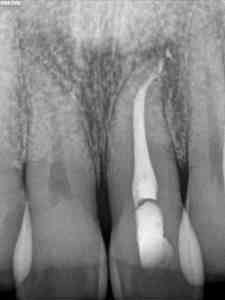

Después de un mes, le volvimos a citar: